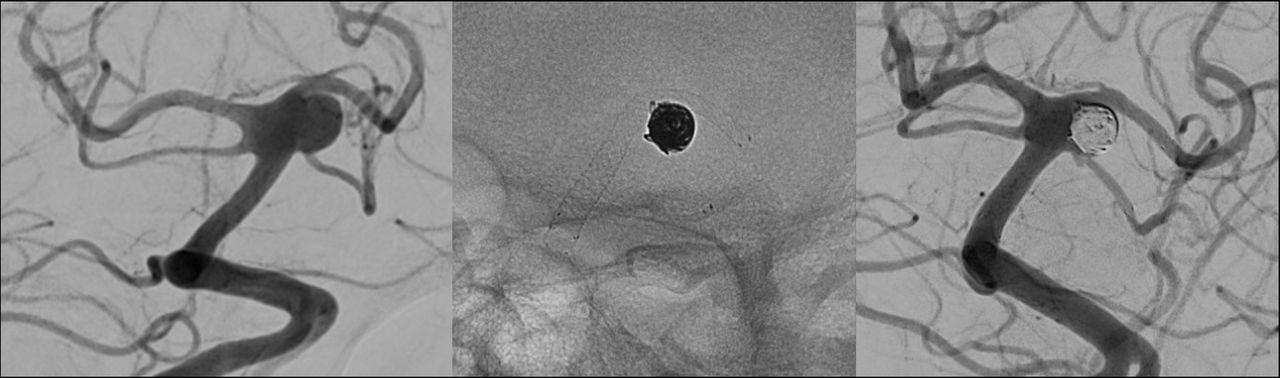

La mia formazione e la mia carriera professionale hanno avuto inizio presso l’Ospedale Niguarda di Milano, dove, per oltre vent’anni, mi sono dedicato con continuità alla diagnosi e al trattamento endovascolare delle patologie vascolari del sistema nervoso centrale. In particolare, ho maturato esperienza nella gestione di aneurismi cerebrali, malformazioni artero-venose, fistole durali, stenosi e trombosi delle arterie e delle vene intracraniche.

Collaborazione con il sito Neuroangio.org, sito di riferimento per i neurointerventisti di tutto il mondo.

https://neuroangio.org/cone-beam-ct-comprehensive-reference-of-principles-and-practice/cone-beam-how-to-do-it-step-by-step-philips/

https://neuroangio.org/cone-beam-ct-comprehensive-reference-of-principles-and-practice/cone-beam-how-to-do-it-step-by-step-philips/cone-beam-ct-philips-complex-aneurysms-flow-diversion-and-stenting/